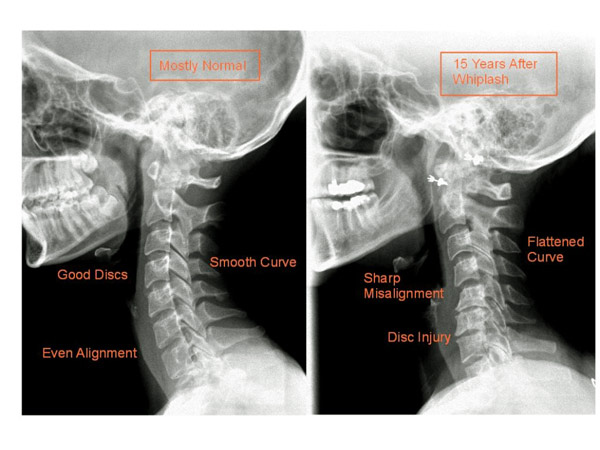

Hình ảnh Xquang cột sống cổ

Hình ảnh Xquang cột sống cổ ít có giá trị trong chẩn đoán xác định bệnh lý thoát vị đĩa đệm cột sống cổ. Tuy nhiên hình ảnh Xquang cột sống cổ có thể gián tiếp gợi ý đến thoát vị đĩa đệm cột sống cổ như cột sống mất đường cong sinh lý, lệch vẹo cột sống, trượt đốt sống ra trước, hẹp khe gian đốt sống… Có thể thấy hình ảnh thoát vị Schmorl biểu hiện là những nốt xơ hóa và lõm vào thân đốt sống. Hình ảnh Xquang chếch 3/4 có thể đánh giá lỗ liên hợp.

Hình ảnh mất đường cong sinh lý

Chúng tôi tiến hành chụp Xquang cột sống cổ thẳng – nghiêng tư thế tĩnh và tư thế động (cúi tối đa, ngửa tối đa) cho tất cả người bệnh thuộc nhóm nghiên cứu. Chúng tôi nhận thấy rằng có 11/30 người bệnh cho hình ảnh mất đường cong sinh lý cột sống cổ chiếm tỷ lệ 36,7% (bảng 1).

Khi nghiên cứu người ta thấy do sự thoái hóa của cột sống cổ, sự co cơ để đối kháng lại triệu chứng đau là nguyên nhân chính gây biến đổi đường cong sinh lý cột sống. Quá trình thoái hóa lâu ngày làm giảm tầm vận động của cột sống gây gù, lệch vẹo cột sống cổ. Những người bệnh này khi phẫu thuật ngoài việc giải phóng chèn ép tủy, rễ thần kinh thì cần cố gắng thiết lập lại giải phẫu sinh lý của cột sống cổ.

Nguyễn Quốc Dũng [1] nghiên cứu 52 người bệnh thoát vị đĩa đệm cột sống cổ tai bệnh viện Việt Đức cho thấy tỷ lệ người bệnh mất đường cong sinh lý cột sống cổ là 84,62%. Hoàng Văn Chiến [2] nghiên cứu tỷ lệ này là 96%. Nguyễn Văn Thạch, Hoàng Gia Du [3] là 26,7%.

Hình ảnh giảm chiều cao khe liên đốt sống

Nghiên cứu của chúng tôi trên 30 người bệnh cho kết quả 15/30 người bệnh có hình ảnh giảm chiều cao khe liên đốt sống tại tầng thoát vị chiếm tỷ lệ 50% (bảng 1).

Đĩa đệm là mô được nuôi dưỡng kém, chủ yếu được nuôi dưỡng bằng cơ chế thẩm thấu do đó quá trình thoái hóa diễn ra nhanh. Qúa trình thoái hóa làm đĩa đệm mất nước, giảm tính đàn hồi. Dưới tác dụng của lực bên ngoài trong quá trình sinh hoạt, lao động làm đĩa đệm xẹp lại và bè rộng ra gây giảm chiều cao đĩa đệm.

Nghiên cứu của Nguyễn Quốc Dũng [1] cho thấy hình ảnh giảm chiều cao khe liên đốt là 56,7%. Nguyễn Văn Thạch, Hoàng Gia Du [3] nghiên cứu thấy tỷ lệ này là 17,2%.